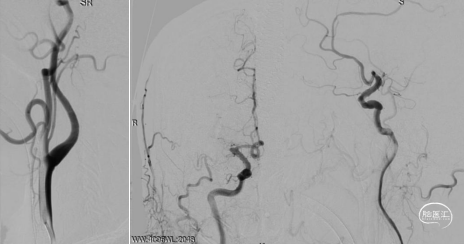

右侧大脑中动脉闭塞。

左侧颈内动脉显影正常,未见向右代偿。

右侧椎动脉优势,未见向前代偿。

考虑到血栓抽吸导管系统(ACE 68)头端抗抽瘪和优异通过性的特点,使用ACE 68快速高到位,微导丝携带微导管Rebar18 超选至R-M2段,造影证实在真腔。

造影考虑ICAS病变,通过微导管Rebar18输送5*30mm Reco取栓支架,施行SWIM技术。